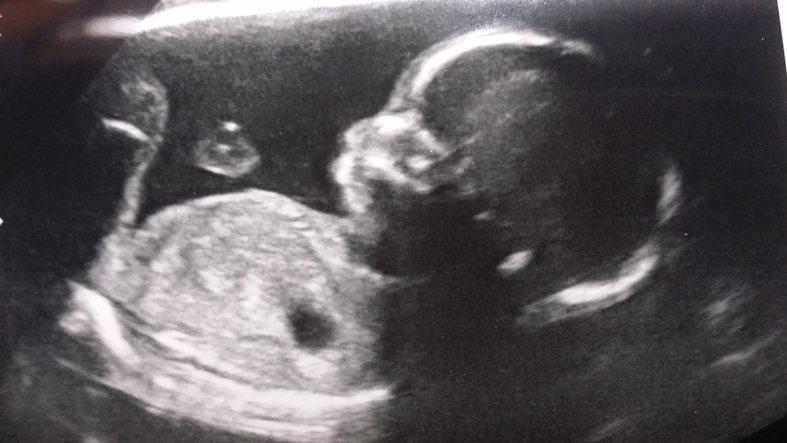

Bring abortion bans to Britain | The Critic Magazine

The move to restrict abortion reflects public opinion on both sides of the pond